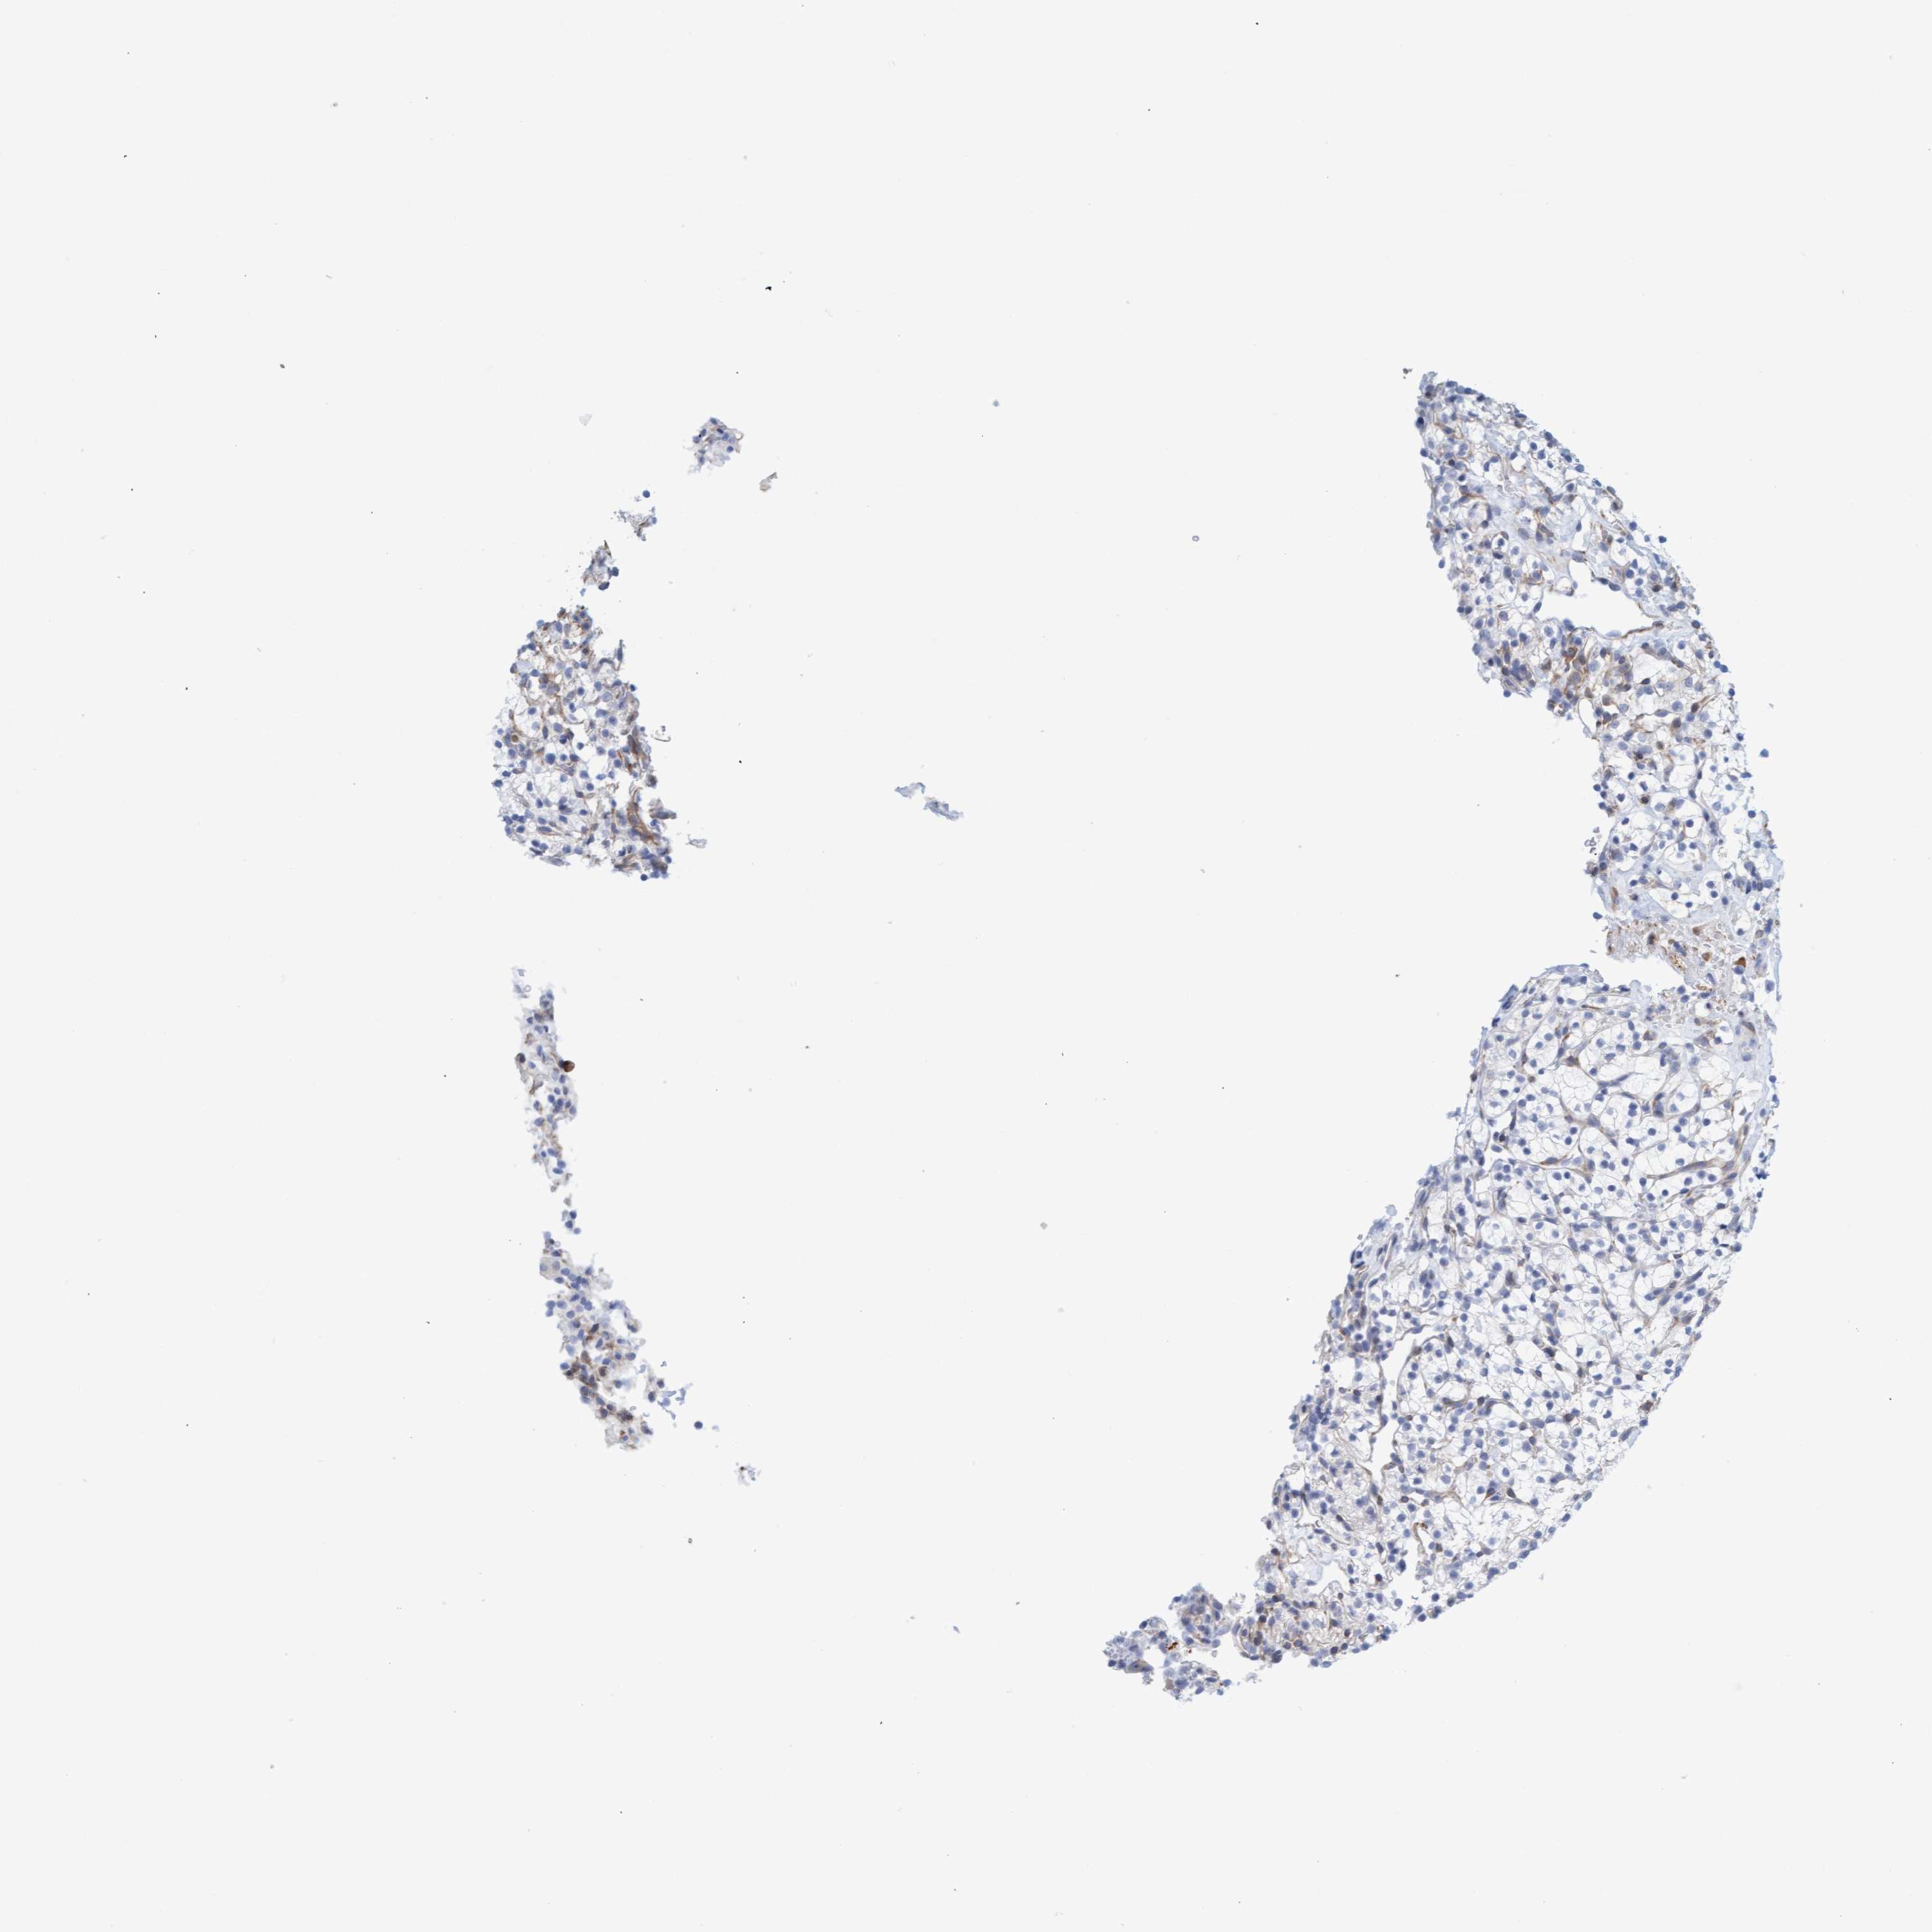

CANCER RENAL CANCER Show tissue menu

KICH TCGA KIRC TCGA KIRC VALIDATION KIRP TCGA PROTEIN RCC CPTAC PROTEIN EXPRESSION